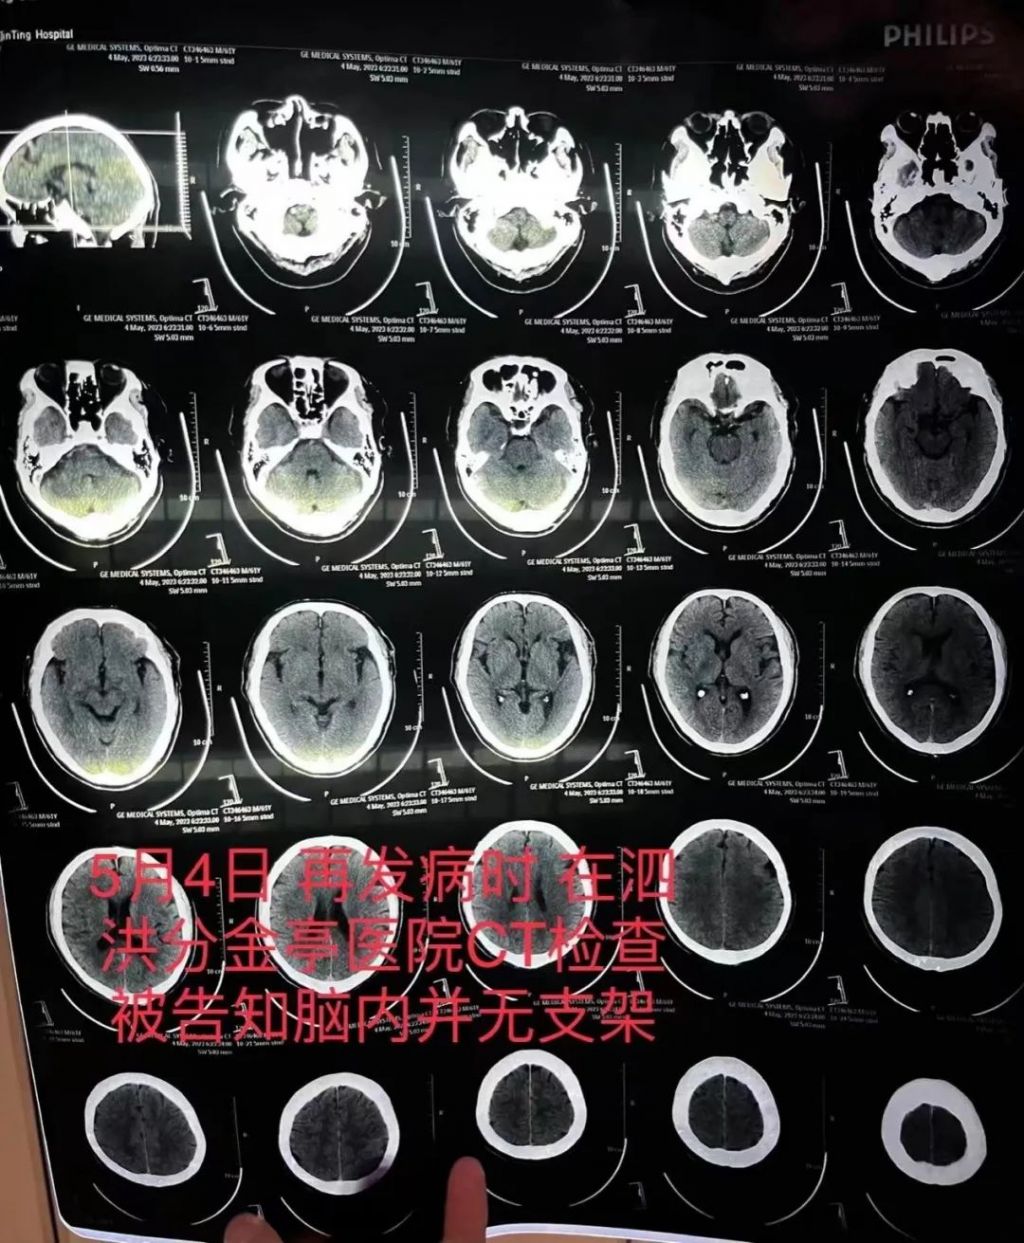

5月4日,朱先生父亲又突发严重脑梗,这距离上次手术不到一个月。他先被救护车送至江苏省宿迁市泗洪县分金亭医院抢救。但这次CT检查发现,其颅内段部分动脉已严重堵闭,同时未发现此前植有支架。